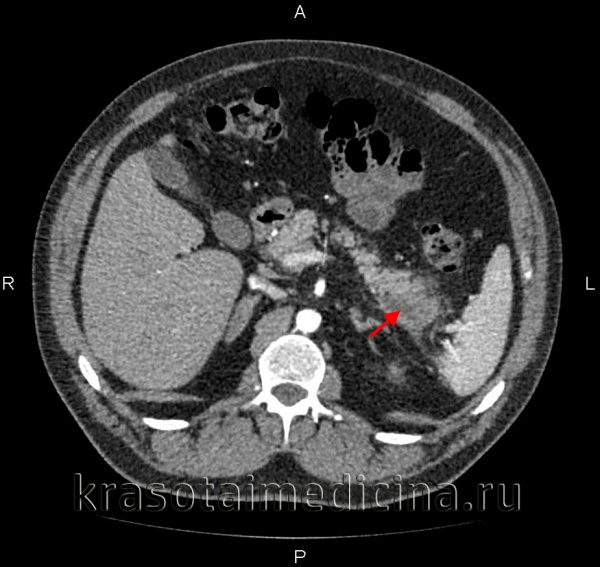

КТ органов брюшной полости. Панкреатит (в области хвоста поджелудочной железы) с наличием отека ее паренхимы, жидкостного содержимого вблизи ее края, на фоне утолщение фасции Героты слева

(Слева) На аксиальной КТ с контрастным усилением у пациента, злоупотребляющего алкоголем, определяется легкое повышение плотности перипанкреатического жира и отек, хотя поджелудочная железа не выглядит яв -но увеличенной в размерах. Эти изменения сопоставимы с отечным панкреатитом, протекающим в легкой форме.

(Справа) На аксиальной КТ с контрастным усилением у пациента после ЭРХПГ и установки стента определяется увеличение поджелудочной железы на фоне ее отека и потери нормальной дольчатой структуры, в сочетании с повышением плотности перипанкреатического жировой клетчатки и наличием жидкости около поджелудочной железы. Изменения сопоставимы с острым отечным панкреатитом. (Слева) На аксиальной КТ с контрастным усилением у пациента с жалобами на боль в животе определяется увеличение и отек поджелудочной железы с наличием жидкости возле нее и повышением плотности окружающей железу жировой ткани - изменения, сопоставимые с острым отечным панкреатитом. Все отделы поджелудочной железы накапливают контраст, признаки некроза отсутствуют.